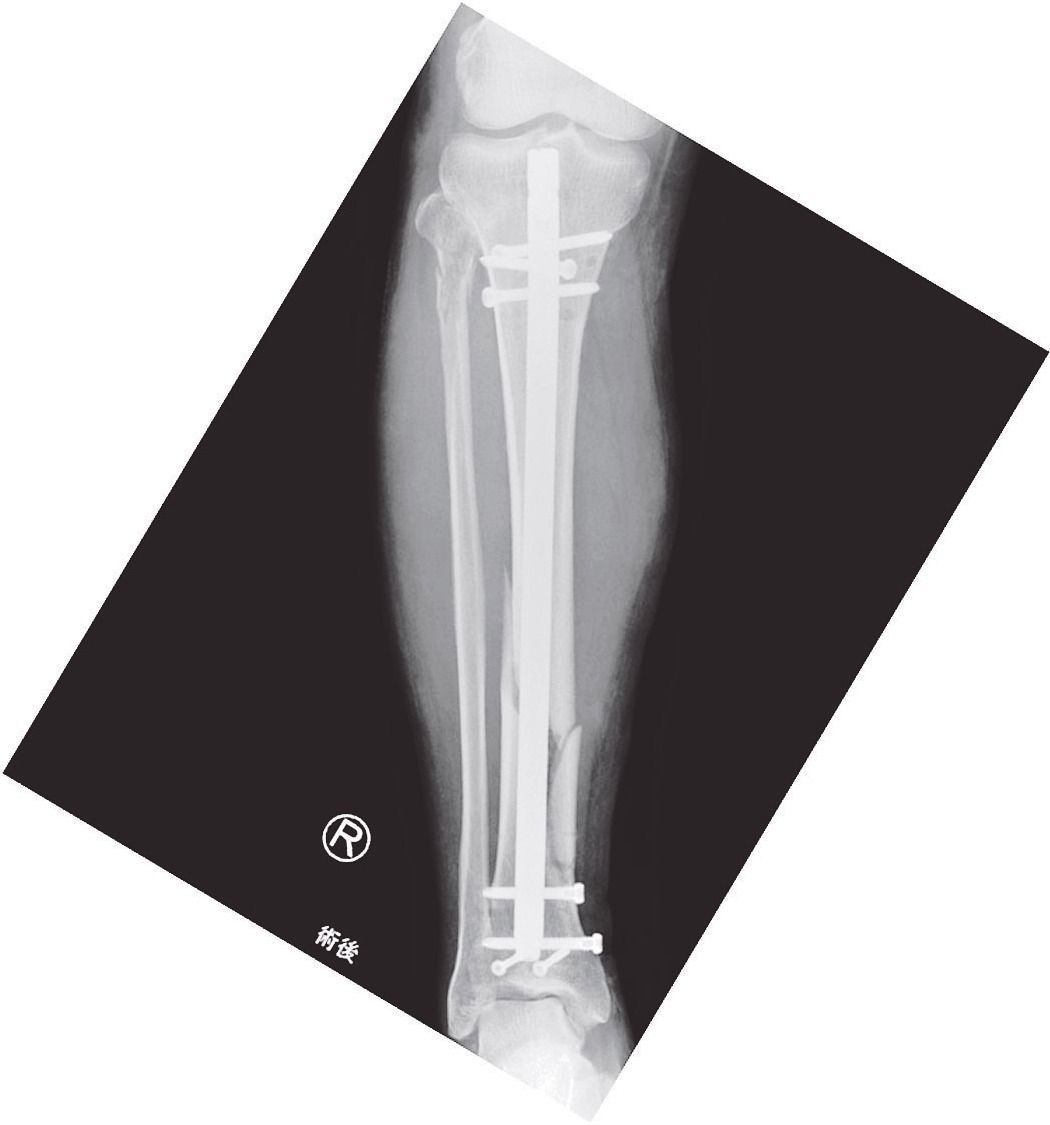

連載「交通安全・医理工連携の今 『世界一』への挑戦」(97)黒住健人 交通事故と外傷(1)外傷と骨折、骨折の機序、治療の概要